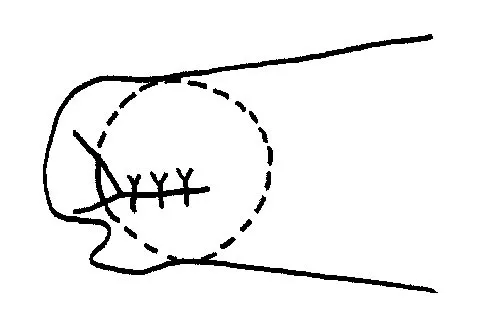

Initial repair of the large U-shaped rotator cuff tear shown in Figure 12 consists of closing the tear side-to-side to take advantage of margin convergence. The most significant biomechanical consequence of this repair step results in

Incorporating the concept of margin convergence during the repair of a massive, U-shaped rotator cuff tear provides which of the following primary biomechanical benefits?